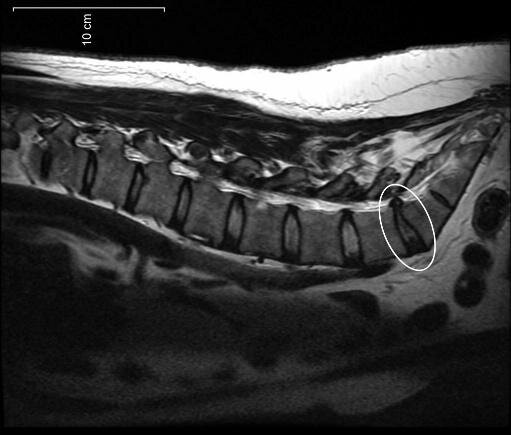

Дегенеративные и дистрофические изменения (разрушение и изменение структуры тканей) являются причиной ухудшения амортизирующей способности диска. В фиброзном кольце появляются дефекты, сквозь которые вещество ядра может смещаться дальше, чем это происходит в норме. Такие выпячивания называют протрузиями. Чаще всего они формируются в области поясницы или, несколько реже, шее.

Если же выпячивание направлено назад (дорзальная/дорсальная/задняя протрузия), то при больших размерах оно может воздействовать на спинной мозг. Обычно такое не происходит благодаря тому, что протрузии довольно маленькие образования, но если они постепенно перерастают в грыжу, то последствия могут быть очень печальными. Примером такого рода осложнений является дискогенная миелопатия, способная привести к параличу конечностей и/или нарушению функций внутренних органов.

Как правило, размеры протрузии варьируются в пределах от 2 до 7 мм, что и позволяет ей долго оставаться бессимптомной. Однако если она появляется в самом узком отделе позвоночника – шейном – то нежелательные последствия наступают уже при диаметре выпячивания всего в 2–3 мм.